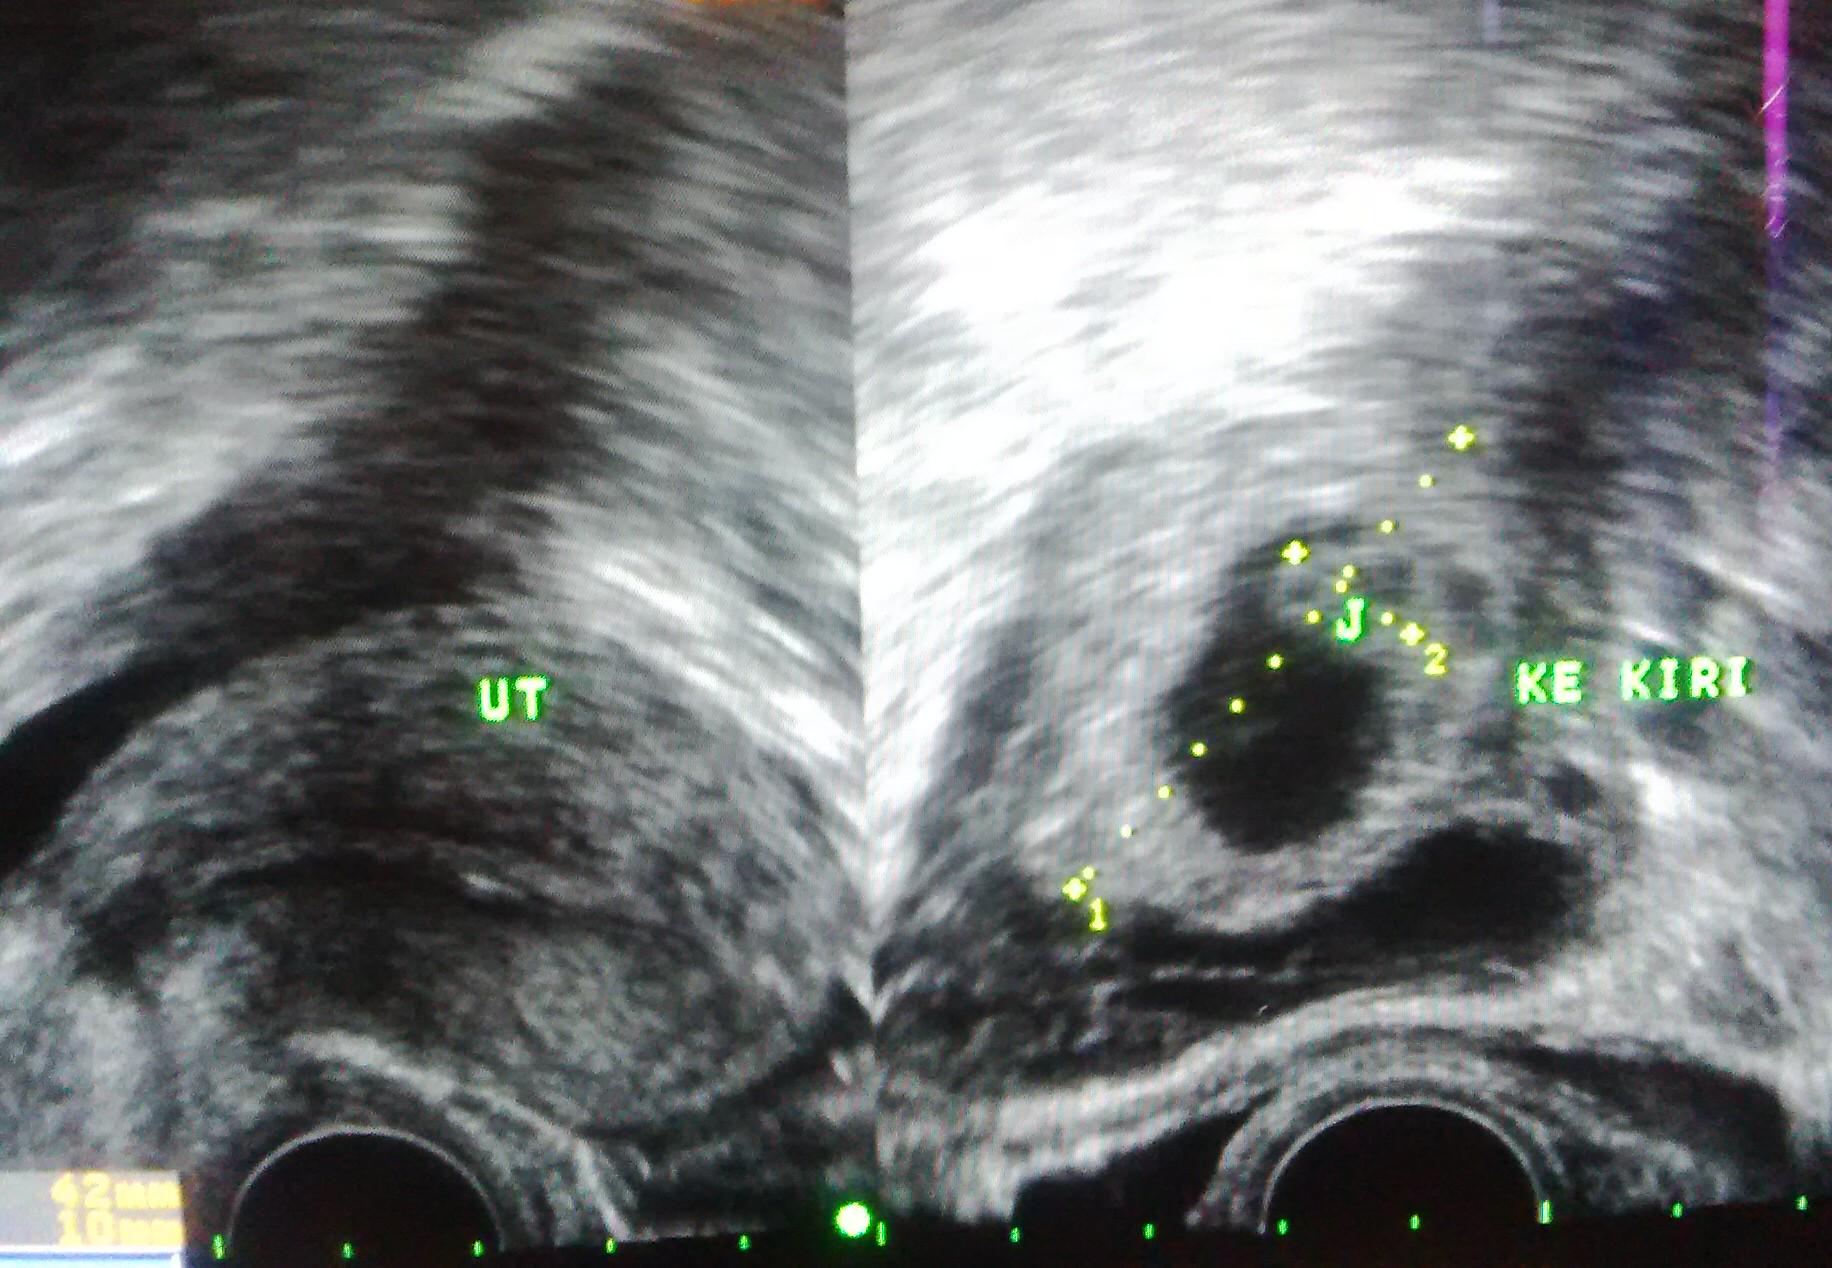

Dr. Prima P,SpOG,MPH on Twitter: “#kehamilan #ektopik diketahui dg pemeriksaan USG. Tampak rahim kosong, kantung kehamilan diluar rahim. Pic » http://t.co/E043Lrw5JJ”

Dr. Prima P,SpOG,MPH on Twitter: “#kehamilan #ektopik diketahui dg pemeriksaan USG. Tampak rahim kosong, kantung kehamilan diluar rahim. Pic » http://t.co/E043Lrw5JJ”